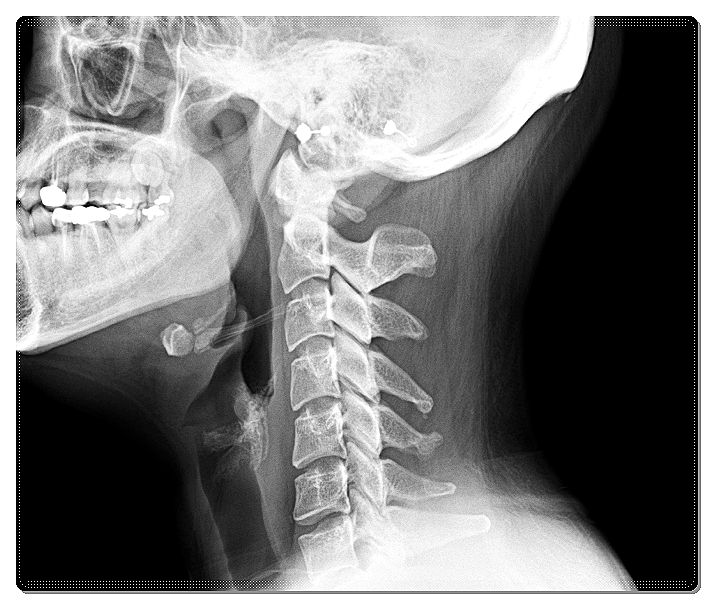

경추, 즉 목뼈는 원래 완만한 C자 곡선을 가지고 있습니다.

이 곡선은 자동차 서스펜션처럼 충격을 흡수하는 역할을 하지요.

그런데 교정이 필요한 경우, 이 곡선이 사라지면서 충격 완화 능력이 떨어집니다.

결과적으로 디스크가 지속적으로 압박을 받으며 목디스크나 퇴행성 질환으로 이어질 수 있습니다.